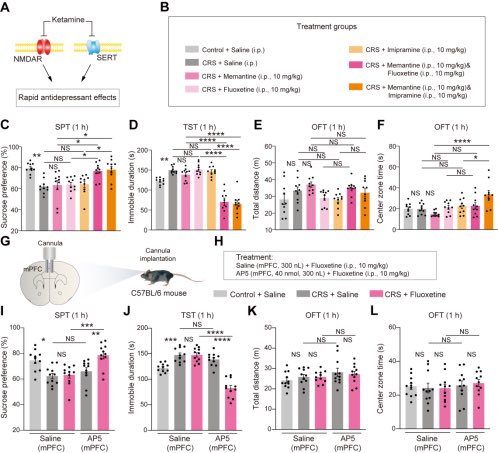

首先,从定义上讲,“反解离(anti-dissociative)”并不是一个标准的医学术语或者广泛认同的药理学分类。在正规资料,比如医学文献、维基百科、精神药理学教科书中,目前并没有“反解离药物”这个正式概念。

看上去像是为了描述某类特定效应而创造的术语(可能是nmda受体活性增强),用来对抗因NMDA受体拮抗剂(比如氯胺酮、DXM、PCP等)引发的解离体验(dissociation)。

那么更常见的是将其归入认知增强剂(cognitive enhancers),特别是改善认知连接性(connectivity)和现实感知(reality testing)的类型。

但其实在药理学上,单纯用“受体激动剂”来逆转“受体拮抗剂”的效应,有时会导致过度激活。

对于NMDA受体而言,过强的NMDA活化本身就与兴奋性毒性(excitotoxicity)和精神病样症状(psychotomimetic effects)有关,比如谷氨酸风暴可以引发严重的焦虑、妄想、乃至癫痫。

也就是说,简单地“激动-解除拮抗”在中枢神经系统是很危险的做法,尤其是对于易感个体(如有精神分裂素质的人)。

科学的处理方式一般是通过更细致的调节,比如微调NMDA/AMPA平衡、调节其他辅助途径(如GABA、5-HT、mGluR受体),而不是简单粗暴地用“NMDA增强剂”去顶回去。